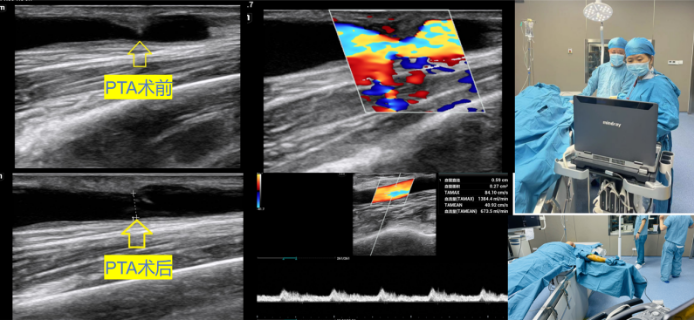

西咸院区肾内科进一步治疗,闫晓辉副主任医师积极安排患者完善相关检查,超声医学中心韦爱华副主任医师认真为患者进行血管评估,发现由于自体动静脉内瘘静脉侧局段狭窄导致该患者血流量明显下降。闫晓辉副主任医师与患者及家属充分沟通,决定为患者进行超声引导下动静脉内瘘狭窄球囊扩张术。

在超声医学中心刘莉主任和穆靓副主任的安排下,韦爱华副主任医师利用便携式超声诊断仪床旁配合闫晓辉副主任医师,为该患者顺利进行自体动静脉内瘘狭窄球囊扩张术。术后恢复良好,狭窄处的管径从1.3mm增宽到4.0mm,进行穿刺内瘘血液透析治疗血流量充足,泵控血流量达250ml/min。